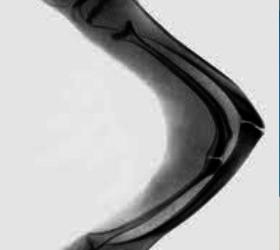

По итогам проведенного исследования было выяснено, что средиземноморская диета с оливковым маслом способствует укреплению костей, а также защите от такого заболевания как остеопороз. Также данная диета помогает снизить риск возникновения переломов и благотворным образом влияет на психическое здоровье человека.